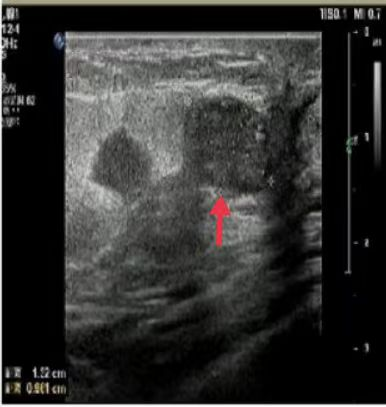

06、**女士,57岁

于2023年10月27日在邯郸仁泰南区体检,乳腺彩超检查提示:右侧乳腺10-11点方向见大小约1.4*0.8cm低至无回声,边界欠清,形态欠规整,右侧乳腺约12点方向见大小约1.3*1.0cm低回声,边界欠清,形态欠规整,内回声不均,右侧腋下见大小约1.0*0.6cm低回声,随即通知客户到三甲医院进一步检查,2023年11月6日电话回访,客户已到石家庄省四院进一步检查明确病变性质。2023年11月30日跟踪回访,客户已在石家庄省四院手术治疗。